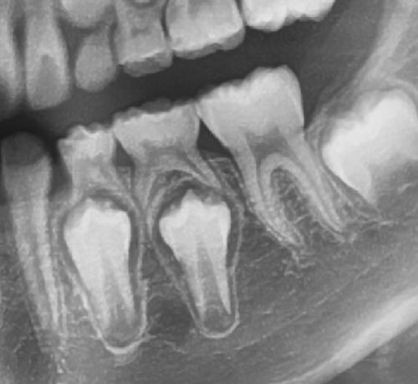

안녕하세요 목동안치과 안상우 원장입니다.오늘은 치아가 흔들리게 된다면 뽑아야만 하는것인지에 대해서 한번 알아 보려고 해요.치아가 흔들리는 증상에 대해 이해하기 위해서는 치주조직에 대한 이해가 우선필요합니다.치아는 잇몸뼈에 고정이 되어 교합압을 담당하게 됩니다잇몸뼈와 치조골 사이에는 치주인대라고 하는 치아를 고정시켜주는 조직이 있습니다. 이 조직에 유격이 발생하거나 하면 치아가 흔들리게 되는거에요.사진과 같이 치아뿌리 주변에는 치조골이 있고 이 치조골을 치주인대가 감싸고 있습니다.치아 뿌리 주변에 하얗게 보이는 것이 치밀화된 골인데요 이 골에 치주인대가 치아 뿌리와 연결되어 치아를 지지하는 역활을 하게 되요.치아가 흔들리는것은 치아에 가해지는 힘과 이 치주인대가 버텨주는 힘이 잘 균형을 이루냐에 있습니다.자 그럼 흔들리는 치아는 뽑아야만 할까요?결론적으로 그렇지 않습니다.치아가 흔들려도 통증과 염증이 없고 정상적으로 교합을 한다면 계속해서 사용할수 있어요.치아가 흔들리는 여러 상황을 한번 가정해 볼께요일단 정상 치주조직에서의 상황입니다.정상적인 치주조직으로 지지되는 치아에 각각의 교합력이 걸렸을경우를 가정해 볼께요 약한힘이나 중간힘까지는 치주가 버텨줄수 있습니다.하지만 너무 강한 힘이 작용하게 되면 치주조직에 손상이 와서 치아가 흔들릴수 있어요.반면 잇몸뼈가 내려간 상황을 한번 볼께요이런 치주조직에서는 가해지는 힘이 약한경우에는 치아가 정상적인 기능을 하게 됩니다하지만 중간정도에 힘에서는 치아가 흔들리게 되고 통증이 생길수도 있어요.강한힘에는 아마도 치아가 탈락을 하겠죠치아가 흔들리거나 해도 치주조직에 염증이 없고 통증이 없으며 치아가 정상적으로 기능을 한다면 계속 사용할수 있어요.흔들리며 통증을 유발하는 치아가 있다면 다음 세가지 경우에 따라서 치료나 관리를 해야 합니다첫번째는 흔들리는 치아 주변에 잇몸에 염증이 있는 경우 입니다.염증은 약한 잇몸을 더 망가뜨릴수 있습니다.염증을 유발하는 치석이 있다면 스케일링이나 잇몸치료를 해야합니다.잇몸에 염증이 생기지 않도록 칫솔과 치실 그리고 치간칫솔로 잘 관리해줘야 해요.두번째로는 치주조직이 버티기 힘든 힘이 치아에 가해졌을 경우입니다.이런경우에는 치아에 가해지는 교합력을 줄이거나 교합간섭을 조정해 줘야 합니다.마지막으로 치아를 잡아 주는 치조골 자체가 염증으로 인해서 완전히 망가져서 치주인대가 존재하지 않는 경우입니다.사진과 같이 잇몸위에 완전히 떠있는 경우를 생각할수 있습니다.이런상태는 이미 몸이 치아를 외부물질로 인식하고 있는것입니다.우리몸에 가시가 박히면 아프고 주변으로 염증이 생기잖아요?몸에 밖힌 가시가 우리의몸과 하나가 되지 않듯이 이미 몸에서 치아를 밀어내고 있는것이기 때문에 이런경우에는 안타깝지만 발치를 해야 해요.발치를 하고 나면 해당부위에 임플란트나 보철치료를 해야 할수 있습니다.어떻셨나요? 치아가 흔들린다면 당황해 하지 마시고 치과에서 진료를 받아보세요.치아가 흔들리는 원인과 치주상태를 평가한다음 관리를 해서 사용할수 있도록 해보세요.